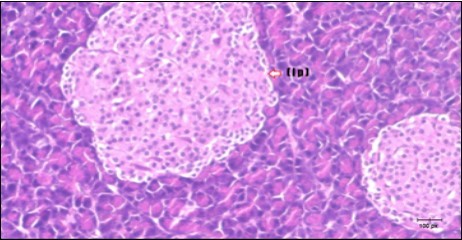

Pancreas Histopathological Observations

Histological examination of pancreas of the control rats showed normal sized islets of pancreas (Ip) compared to the diabetic rats which showed markedly atrophic islets of pancreas (I.p.) (Figure 8 and Figure 9). Pancreas of in groups (3) and (4) rats showed mild atrophic islets of pancreas (I.p.) with inflammatory cellular infiltrate (Figure 10 and Figure 11). The pancreas of rats in group (5) showed nearly normal islets of pancreas (I.p.) with few inflammatory cellular infiltrate (I.c.) (Figure 12).

Figure 9.Photomicrogragh of pancreas section of diabetic rat showing the markedly atrophic islets of Langerhans. (arrow) (H&E) (40X).

Figure 10.Photomicrogragh of pancreas section of treated rat with Fenugreek showing less improved islets of Langerhans with more cells (star). (H&E) (40X).

Figure 11.Photomicrogragh of pancreas section of treated rat with Glimepiride showing mildly improved of isled of Langerhans with large number of cells (dashed-arrow). (H&E) (40X).

Figure 12.Photomicrogragh of pancreas section of treated rat with both Fenugreek and Glimepiride showing nearly normal islets of Langerhans with spindle (arrow) & polygonal cells (dashed- arrow). (H&E) (40x).

Histopathological observation in diabetic control showed degenerative changes in both endocrine and exocrine pancreases. A probable explanation may be related to oxidative stress resulting from hyperglycemia which decreases the antioxidants levels and increases ROS 33 and the activities of antioxidant enzyme were altered in diabetic rats. These effects further exacerbate the development and progression of diabetes complications and these may represent the causes of degeneration revealed in histological sections. Fenugreek improved blood glucose levels and insulin, lowered pancreatic islet and β-cells damage which may be attributed to its immune modulatory activity and insulin stimulation action along with its antioxidant potential 32. Glimepiride caused restoration of morphology of beta cell of diabetic and it increased percentage of beta cells 34. This protective effect could be attributed to the antioxidant properties of Glimepiride. Combination therapy improves the protective effect of both therapies alone.